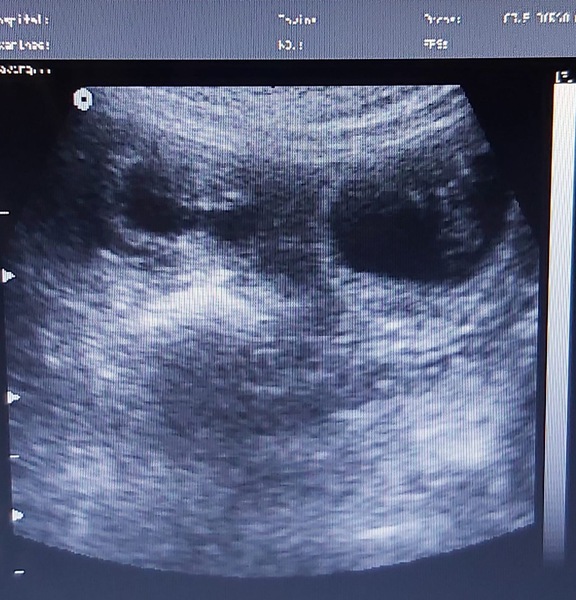

Mit Freude geben wir die Trächtigkeit unserer Bea bekannt, die der Ultraschall heute bestätigte.

So alles weiterhin gut verläuft,  erwarten wir Mitte Februar vielversprechende  Welpen in zw u. tricolor von